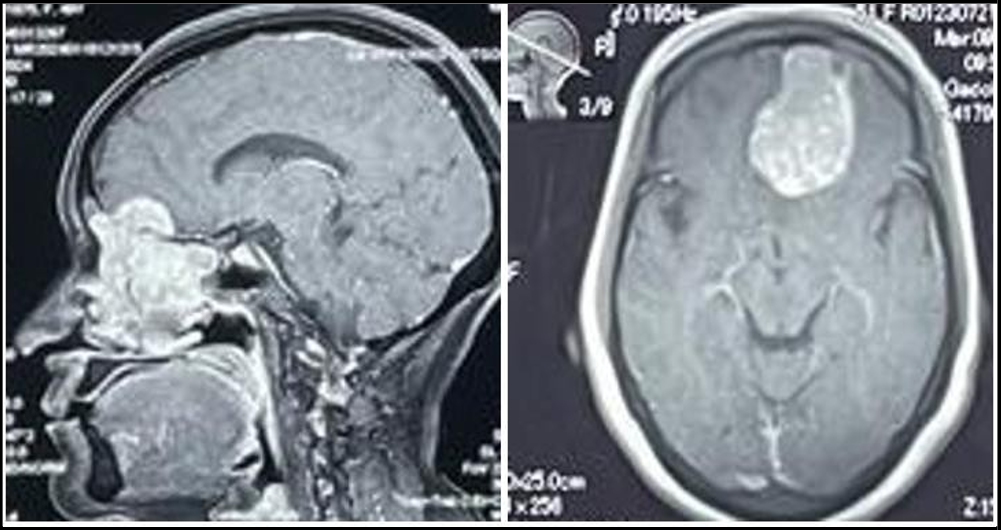

She began experiencing relapsing symptoms, including persistent headaches lasting for a week, prompting a neurosurgical evaluation to assess the possibility of recurrence of his previously diagnosed condition. A contrast-enhanced MRI of the brain was performed to evaluate for any mass effect that could account for the headaches. On physical examination, papilledema was noted, and signs of raised intracranial pressure (ICP) were confirmed on MRI. MRI Brain plain and contrast reveals two heterogeneously enhancing lesions in the right anterior fronto-parietal regions (Figure 3 and 4). Both lesions were found to be overlapping each other. First lesion is larger solid cum cystic, extra axial showing avid heterogeneous post contrast enhancing lesion along right anterior parietal convexity causing effacement of right lateral ventricle and vasogenic edema surrounding brain parenchyma. Second smaller lesion showing bony infiltration of the overlying anterior parietal skull vault, extraaxial and slightly hypo enhancing.

Figure 3 and 4: MRI Brain with contrast showing coronal and Axial views revealing an extra axial neoplastic metastatic lesion seen along the right anterior parietal convexity with contralateral midline shift of 9.8mm.